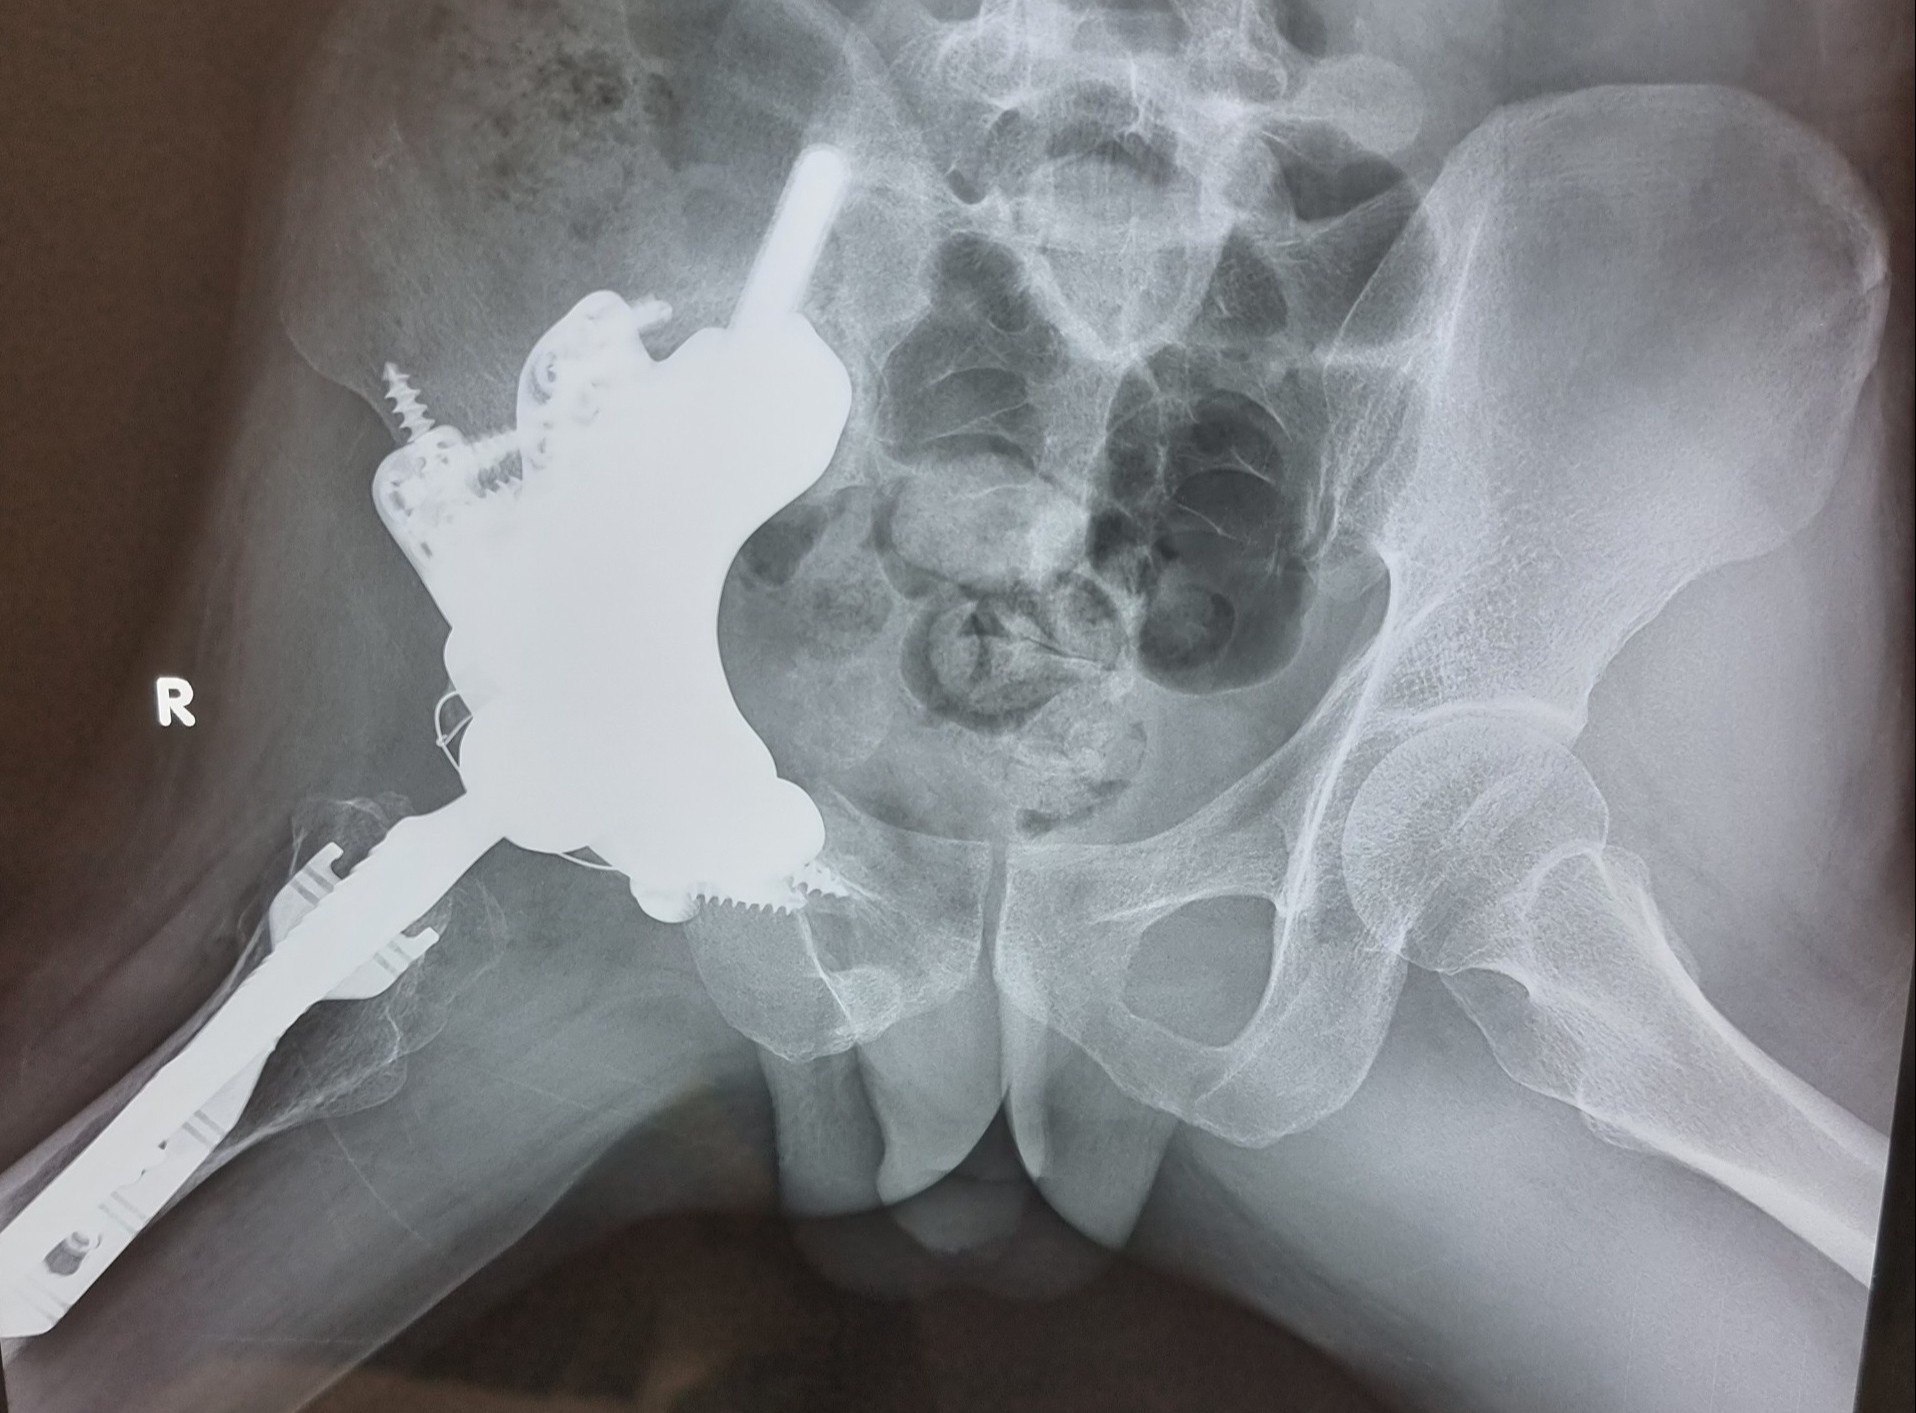

khop hang bang titanium anh 3

Hình ảnh X-quang vùng khung chậu - khớp háng sau mổ 3 tháng của bệnh nhân. Ảnh: BSCC.

Sau 10 giờ, các bác sĩ đã bóc tách thành công và tạo hình khớp háng - xương chậu cho bệnh nhân Hội. Theo TS Tuấn, đây là trường hợp đầu tiên tại Việt Nam phẫu thuật thành công tạo hình cá thể hóa khớp háng - xương chậu do bướu nguyên bào sụn hiếm gặp ở vùng chậu - ổ cối.

Quá trình hồi phục của anh Hội diễn ra thuận lợi, xương phát triển tốt. Dự kiến trong vài tháng tới, bệnh nhân có thể đi đứng bình thường.